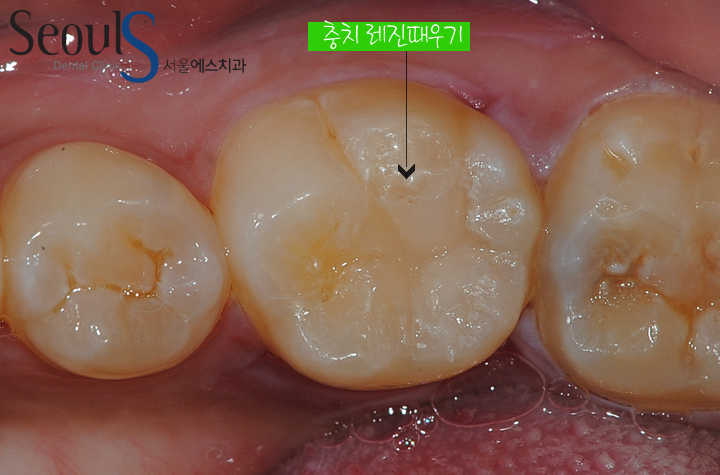

20161124_amal-5 충치 제거 후 빈 공간을 때워 치료를 마쳤습니다 티안나고 주변치아와 잘 어울리게 치료를 마친 모습입니다